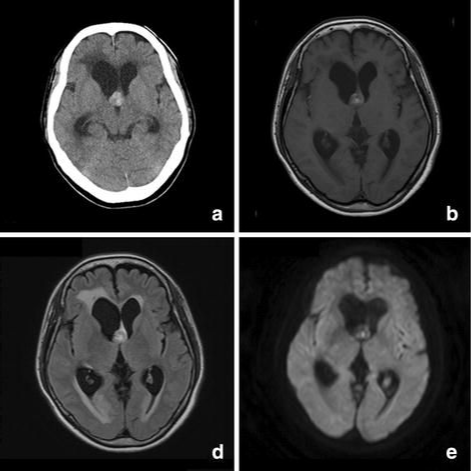

脑海绵状血管瘤无症状或者偶然发现,需要手术吗?脑海绵状血管瘤常会因非特异性或无关症状而做影像学检查时被发现(图1)。对于无症状的脑干海绵状血...